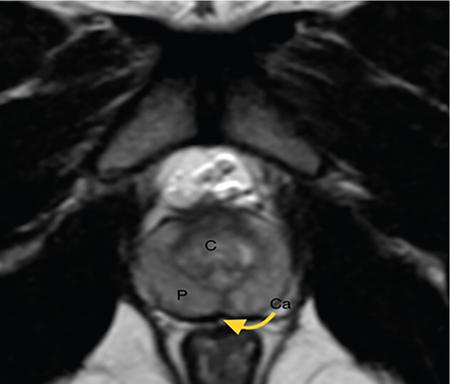

IMAGING ANATOMY OF MALE REPRODUCTIVE SYSTEM Ganesh Rajagopal The male reproductive system is formed by testes, ejaculatory ducts, seminal vesicles (SVs), prostate and penis. Various diagnostic imaging modalities like ultrasound (US), computed tomography (CT), magnetic resonance imaging (MRI) and positron emission tomography (PET) are helpful in the diagnostic evaluation of male reproductive system. Various indications for imaging may include acute scrotum (testicular torsion, trauma and epididymo-orchitis), scrotal swelling (hydrocele, spermatocele, idiopathic scrotal wall oedema and scrotal abscess) and infertility. US and MRI are the commonly used imaging modalities in male reproductive system which complement each other. CT is not very useful due to poor contrast resolution. Ultrasound imaging (US) with a high-frequency linear (7.5–10 MHz) transducer probe has become the imaging modality of choice for scrotal evaluation. Scrotal US is an excellent imaging modality as it can demonstrate abnormalities in testis as well as in paratesticular structures. Scrotal wall is formed by the skin, superficial fascia, dartos muscle, the external spermatic fascia, cremasteric fascia and the internal spermatic fascia. The scrotum is divided into two cavities by a median raphe. This multilayered scrotal wall is poorly delineated in US and MRI, it is typically hypointense on both T1- and T2-weighted images. Testes are paired organs, located normally in scrotal sac, suspended by the spermatic cords. Each testis is examined in orthogonal transverse and longitudinal planes, with both grey scale and colour Doppler modes, to assess its volume and blood flow. Volume of testis is calculated by length × height × width × 0.71. A total volume (both testes) of >30 mL and a single testicular volume of 12–15 mL is generally considered normal for adults. Testes are supplied by the testicular arteries, which arise from the aorta and enter the spermatic cord at deep inguinal ring to reach the upper pole of testis. Pampiniform plexus of veins surrounds the testis and appears as a serpiginous tubular structure posterior to it, measuring >2–3 mm in diameter. Testes are oval shaped, with homogeneous echotexture on grey scale US. Along with the epididymis, they are surrounded by an echogenic capsule, known as the tunica albuginea. Tunica albuginea is covered by tunica vaginalis, which is a remnant of the processus vaginalis and both represent closed sac of peritoneum with two layers. This tunica albuginea is seen extending into posteromedial testis and form the mediastinum testis (Fig. 11.2.1.1), which consists of ducts, nerves and blood vessels. The mediastinum testis is seen as a thin echogenic band. Rete testis is formed by the convergence of seminiferous tubules, seen as a hypoechoic area adjacent to mediastinum testes. The epididymis is a comma-shaped, elongated structure placed at the posterior border of the testis, which drains the efferent ductules (Fig. 11.2.1.2). It has head, body and tail. The head overlies the superior pole of the testis and is isoechoic or slightly hyperechoic whereas, the body and tail are located behind and along the inferior pole and are usually isoechoic. The tail of the epididymis continues into vas deferens (VD), which along with the nerves, lymphatic and vascular structures, forms the spermatic cord (Fig. 11.2.1.3). The spermatic cord appears as an echogenic band in the inguinal canal. The normal adult testis is a homogeneous oval structure that appears hyperintense on T2-weighted sequences and hypointense–isointense on T1-weighted images (Fig. 11.2.1.4). The tunica which surrounds the testis is hypointense T1- and T2-weighted sequences. Epididymis is isointense on T1-weighted images but hypointense on T2-weighted images compared to testis (Fig. 11.2.1.5). Both testicles and epididymis enhance after intravenous administration of gadolinium (Gd) MR contrast agents. Prostate, though visualized by transabdominal scan is better assessed by transrectal high frequency (7.5–10 MHz) ultrasound transducer (TRUS) with patient in left lateral decubitus position. The prostate gland is divided into the anterior fibromuscular stroma (devoid of glandular tissue), transition zone, central zone, periurethral zone and peripheral zone. The base of the prostate is located superiorly and contiguous with the bladder neck whereas, the apex of the prostate is located at the inferior aspect continuous with the striated muscles of the urethral sphincter. The neurovascular bundle is seen to course near the posterolateral aspect of prostate, which is a preferential route of tumour spread. The prostate appears as a cone-shaped organ and shows uniform low echogenicity (Fig. 11.2.1.6). The outer gland (central and peripheral zones) is generally more echogenic than the inner gland. The transition and central zones of the prostate have similar MR signal intensity and cannot be differentiated, hence, are collectively referred as the central gland. On T2-weighted MR images, the normal peripheral zone is homogeneously hyperintense, whereas the central gland tissue is typically hypointense or isointense compared to the skeletal muscle (Fig. 11.2.1.7). The capsule and the anterior fibromuscular stroma appear hypointense on T2-weighted MR images. The SVs are seen as septate tubular cystic structures, appearing uniformly anechoic in US, above the prostate with distal portion of VD is seen medial to it. The duct of SV and VD joins to form the ejaculatory duct, which drains into the prostatic urethra via verumontanum. SVs show ‘bow-tie’ appearance in transversal scans, and a club or tennis-racket shape in longitudinal scans (Fig. 11.2.1.8). On MR, SVs are seen as elongated fluid-containing structures with thin septa, which is hypointense on T1 and hyperintense on T2-weighted MR images (Fig. 11.2.1.9). The VD is seen as a tubular structure with low signal intensity in both T1- and T2-weighted images, on either side. The dilated distal portion of VD (ampulla), appears hyperintense on T2-weighted images, similar to that of the SV due to the fluid content (Fig. 11.2.1.10). The penis, being a superficial organ, is usually examined with US, although MRI is reserved as problem solving modality. The penile body contains two paired muscles – corpora cavernosa and a corpus spongiosum. The former performs as a main erectile body while the latter contains the penile urethra (Fig. 11.2.1.11). Dartos fascia forms the outer layer and the Buck fascia forms the inner layer, which contain the deep dorsal vein (DDV) and a paired dorsal neurovascular bundle. The corpus spongiosum and corpora cavernosa are of high signal intensities on T2-weighted MR images and intermediate-low signals on T1-weighted MR images. The tunica albuginea being a fibrous sheath, surrounds all the three muscles, is hypointense on all sequences (Fig. 11.2.1.12). IMAGING ANATOMY OF FEMALE REPRODUCTIVE SYSTEM Saranya The female reproductive system comprises of uterus, cervix, fallopian tubes, ovaries, vagina and vulva. Ultrasonography (transabdominal and transvaginal) is the primary imaging modality of choice for imaging the female pelvis. Computed tomography (CT) is less often used for pelvic imaging. It provides a quick and systematic overview with coverage of the abdomen in the same session. Hence, CT is well suited for staging pelvic cancers and for imaging gynaecologic and nongynaecologic diseases presenting with acute abdominal pain. Pelvic anatomy is well demonstrated by magnetic resonance imaging (MRI). The contrast resolution of T2-weighted images form the basis for superb tissue characterization of MRI. Uterus is a thick-walled fibromuscular organ composed of myometrium and endometrium. It has two major divisions, namely, the body (corpus) and cervix. The fundus lies above the ostia of fallopian tubes. The normal uterus measures between 5 and 9 cm in length and is in an anteverted position, in relation to the urinary bladder. The myometrium shows three layers on USG, a compacted thin, hypoechoic inner layer forms subendometrial halo, a thicker, homogenously echogenic middle layer and a thinner, hypoechoic outer layer (peripheral to arcuate vessels). The appearance of the endometrium varies with the phase of the menstrual cycle. It appears as a thin echogenic line early in the proliferative phase and shows hypoechoic thickening (4–8 mm) as proliferative phase progresses. It shows a triple layer (sandwich or trilaminar) appearance in the mid cycle and may measure up to 12–16 mm. During secretory phase after ovulation, the layers are seen hyperechoic due to the increasing complexity of glandular structure and secretions (Fig. 11.2.2.1). Postmenopausally, the endometrium decreases in thickness. Endometrial thickness of 5 mm is taken as cut-off. Women on hormonal therapy acceptable endometrial thickness is up to 8 mm. Three-dimensional US permits multiple views to be reconstructed from a single sweep through the uterus. Sonohysterogram is the study of choice for detailed evaluation of the endometrial cavity pathologies. The cervix begins at the inferior narrowing of the uterus (isthmus) at the internal os, which is identified by the entrance of uterine vessels. It has supravaginal and vaginal portions. It is 3–4 cm long and shortens after childbirth. In premenarche women, cervix is larger than corpus, forming approximately 2/3 of the uterine mass. During menarche, there is preferential growth of the corpus and in nulliparous women, corpus and cervix are roughly equal, whereas in parous woman, corpus forms approximately 2/3 of the uterine mass. Uterus is an extraperitoneal organ. The peritoneum extends over urinary bladder dome to anterior uterus, forming anterior cul-de-sac (vesicouterine pouch) and posteriorly, the peritoneum extends more inferiorly to the upper portion of vagina, forming the posterior cul-de-sac (pouch of Douglas, rectouterine pouch), which forms the most dependent portion of the female pelvis. Supporting ligaments of the uterus comprise mainly of broad ligaments, which extend laterally to the pelvic wall and round ligaments, which arise from uterine cornu near fallopian tubes to course anteriorly, pass through the inguinal canal to insert on the labia majora. Connective tissue thickening at the base of the broad ligament forms the uterosacral ligaments posteriorly, cardinal ligaments laterally and vesicouterine ligaments anteriorly. CT examination displays the uterus as a triangular or ovoid soft tissue structure behind the urinary bladder (Fig. 11.2.2.2). Following the administration of intravenous contrast, there is enhancement of myometrium that helps to delineate the endometrium. The vagina, cervix and corpus can be differentiated by morphological characteristics and enhancement pattern. The uterine corpus is typically triangular, whereas cervix is more rounded. The vagina has an appearance of flat rectangle at the level of fornix. The broad ligament and round ligaments are seen coursing laterally and anteriorly, respectively. The main source of vascular supply to uterus is from the uterine arteries. The uterine arteries pass within the broad ligament to enter the uterus, adjacent to the lateral fornices. The uterine artery passes over the ureter at the level of the cervix. Then it courses superiorly, along the lateral margin of the uterus and anastomoses with the ovarian artery. Uterine arteries give rise to arcuate arteries, which run in the outer third of myometrium. Radial arteries extend through the myometrium, which terminate as spiral arteries in the endometrium. The venous system parallels the arterial system, forms a complex venous network in the parametrium and drains to the iliac veins. Middle and lower thirds of the uterus are drained by obturator, parametrial and paracervical lymph nodes. Lymphatic drainage from the upper corpus and fundus goes to the common iliac and paraaortic lymph nodes. MRI provides a more comprehensive view of the uterine anatomy. On MRI, the uterus and cervix show uniform low to intermediate signal on T1-weighted images. On T2-weighted images, uterus shows three distinct zones, namely high signal endometrium, low signal junctional zone and intermediate signal myometrium (Fig. 11.2.2.3). The normal thickness of the junctional zone varies from 2 to 8 mm. A thickness of 9 to 12 mm is equivocal and greater than 12 mm is abnormal. Both endometrium and junctional zone become thin with oral contraceptive intake. Endometrial atrophies and the junctional zone is absent in postmenopausal women. The endocervical canal shows high signal on T2-weighted images, whereas cervical stroma shows low signal, contiguous with the junctional zone. An outer layer of intermediate signal smooth muscle is present. Nabothian cysts representing obstructed, mucous secreting glands are commonly seen as low signal on T1-weighted images and high signal on T2-weighted images. Parametrium shows low to intermediate signal intensity on T1-weighted images and variable signal intensity on T2-weighted images. The round ligaments and uterosacral ligaments show low signal intensity, cardinal ligaments and associated venous plexuses show high signal intensity on T2-weighted images. Ovaries are located posterolateral to the body of the uterus between the uterus and the pelvic sidewall. The internal iliac vessels lie immediately posterior to the ovary. Exact position is variable due to the laxity in the ligaments, parity, uterine size and position. On USG, medulla of the ovaries is mildly hyperechoic compared to the hypoechoic cortex. Developing follicles appear anechoic (Fig. 11.2.2.4). Corpus luteum may have a thick, echogenic ring and haemorrhage is common.